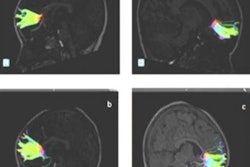

The newly funded BCP will build upon the Multivisit Advanced Pediatric (MAP) Brain Imaging Study for Characterizing Structural and Functional Development, led by Lin. The study's goal was to detail the normal trajectory of different brain structures and how brain functions evolve over this critical time period, using a longitudinal imaging design with a short time interval (three months) between two adjacent imaging sessions. Among the discoveries, Lin and colleagues found that the brain undergoes highly spatiotemporal changes during the first year of life.

"We need to know how these different functional areas develop," Lin said. "MRI allows us to characterize the morphological changes, such as brain volume, as well as functional changes in various brain circuits, such as the motor area, the visual area, and the default mode networks, and how they develop with age during early brain development."